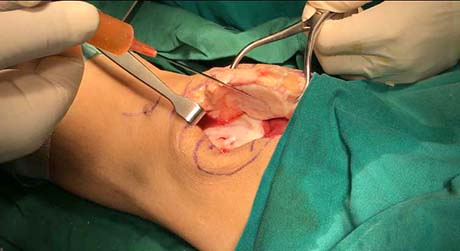

Severe femoral trochlea arthritis, (Outerbridge VI stage). Curetage and preparing for autologous stem cells implantation

Autologous stem cells implantation in the cartilage lesion of the patella and trochlea